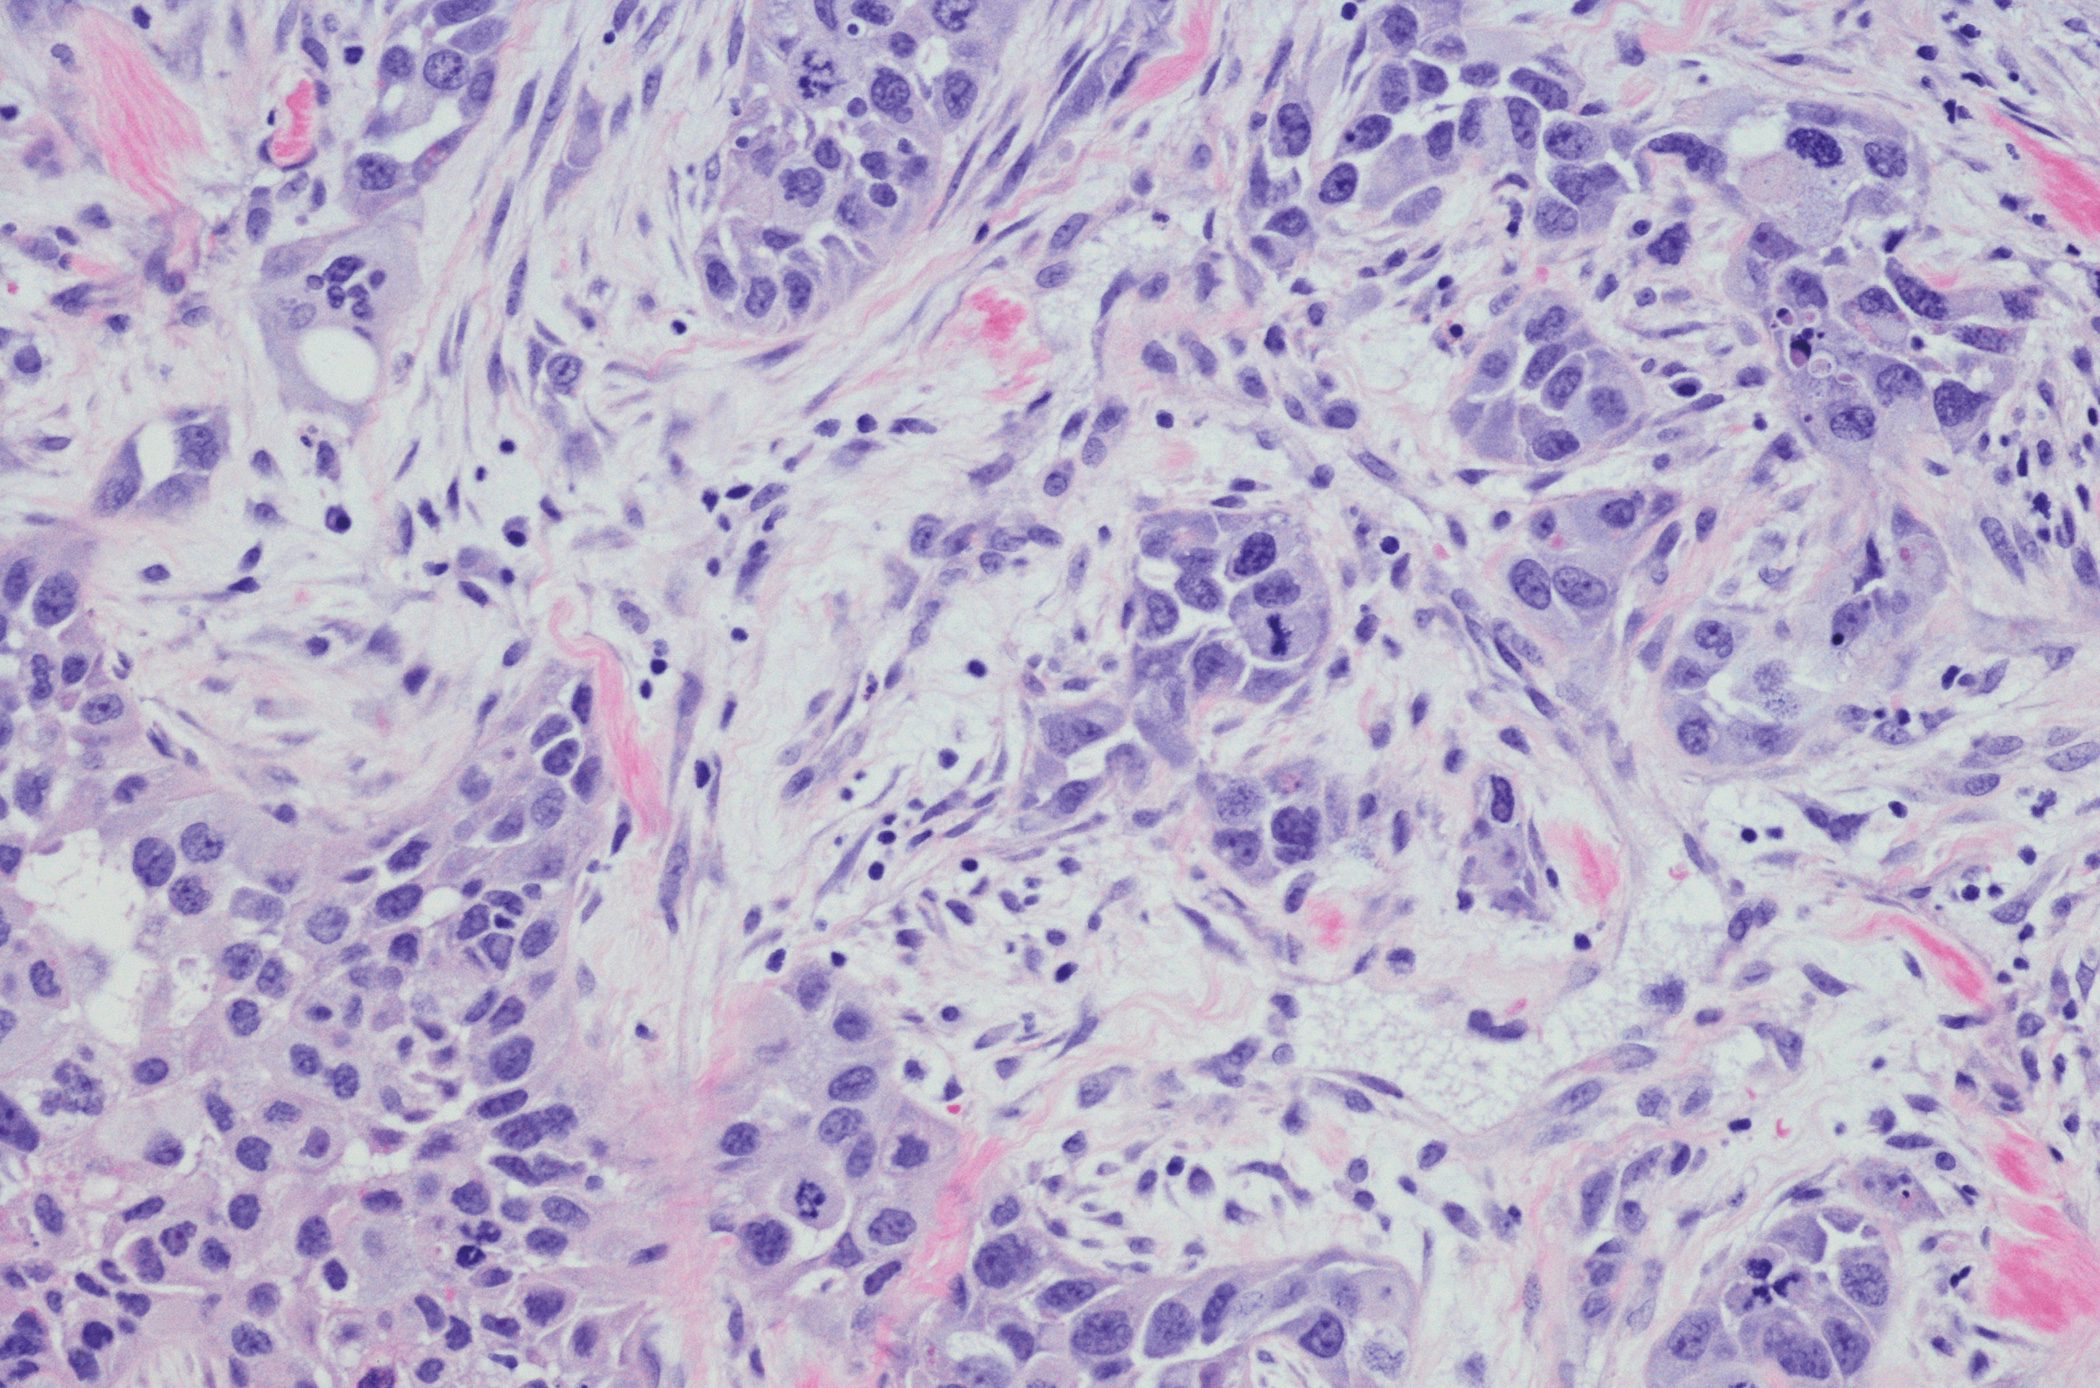

A prevalência de urticária ao longo da vida é de quase 20%. Os anti-histamínicos de segunda geração são também recomendados como tratamento de primeira escolha para os doentes pediátricos. No entanto, os doentes pediátricos com pápulas pruriginosas nem sempre sofrem de uma forma (clássica) de urticária, como mostram claramente os relatórios do hospital pediátrico e a literatura especializada.